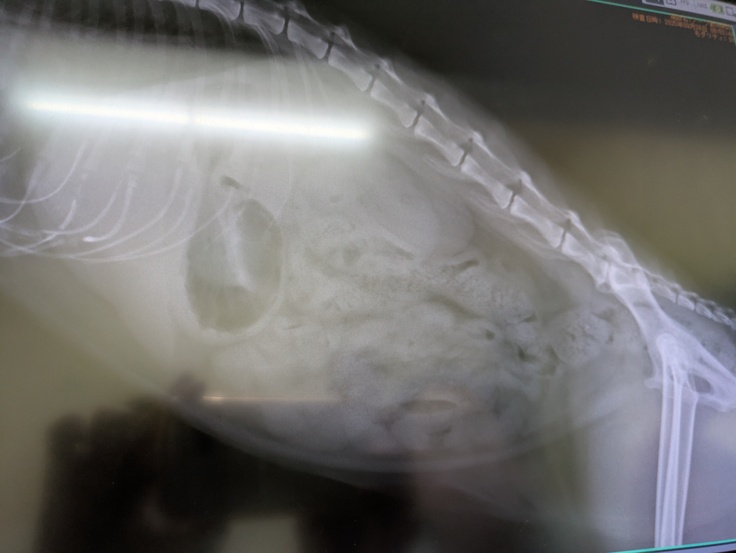

そして本日は[ちゃいろちゃん]の受診日。

とても凶暴なので麻酔下で出来る限りの検査をすることになりました。

一番はウイルス検査。残念ながらエイズは陽性でした。

そして一般血液検査。

前回よりほとんど全ての数値が改善されていました。

ただ1点尿素窒素が高かったのですが腎臓に関わる他の数値は正常とのこと。

レントゲンも撮っていただき、若い猫の腎臓と変わらないとのことで問題なし。

膀胱、尿道も全て問題ないとのこと。